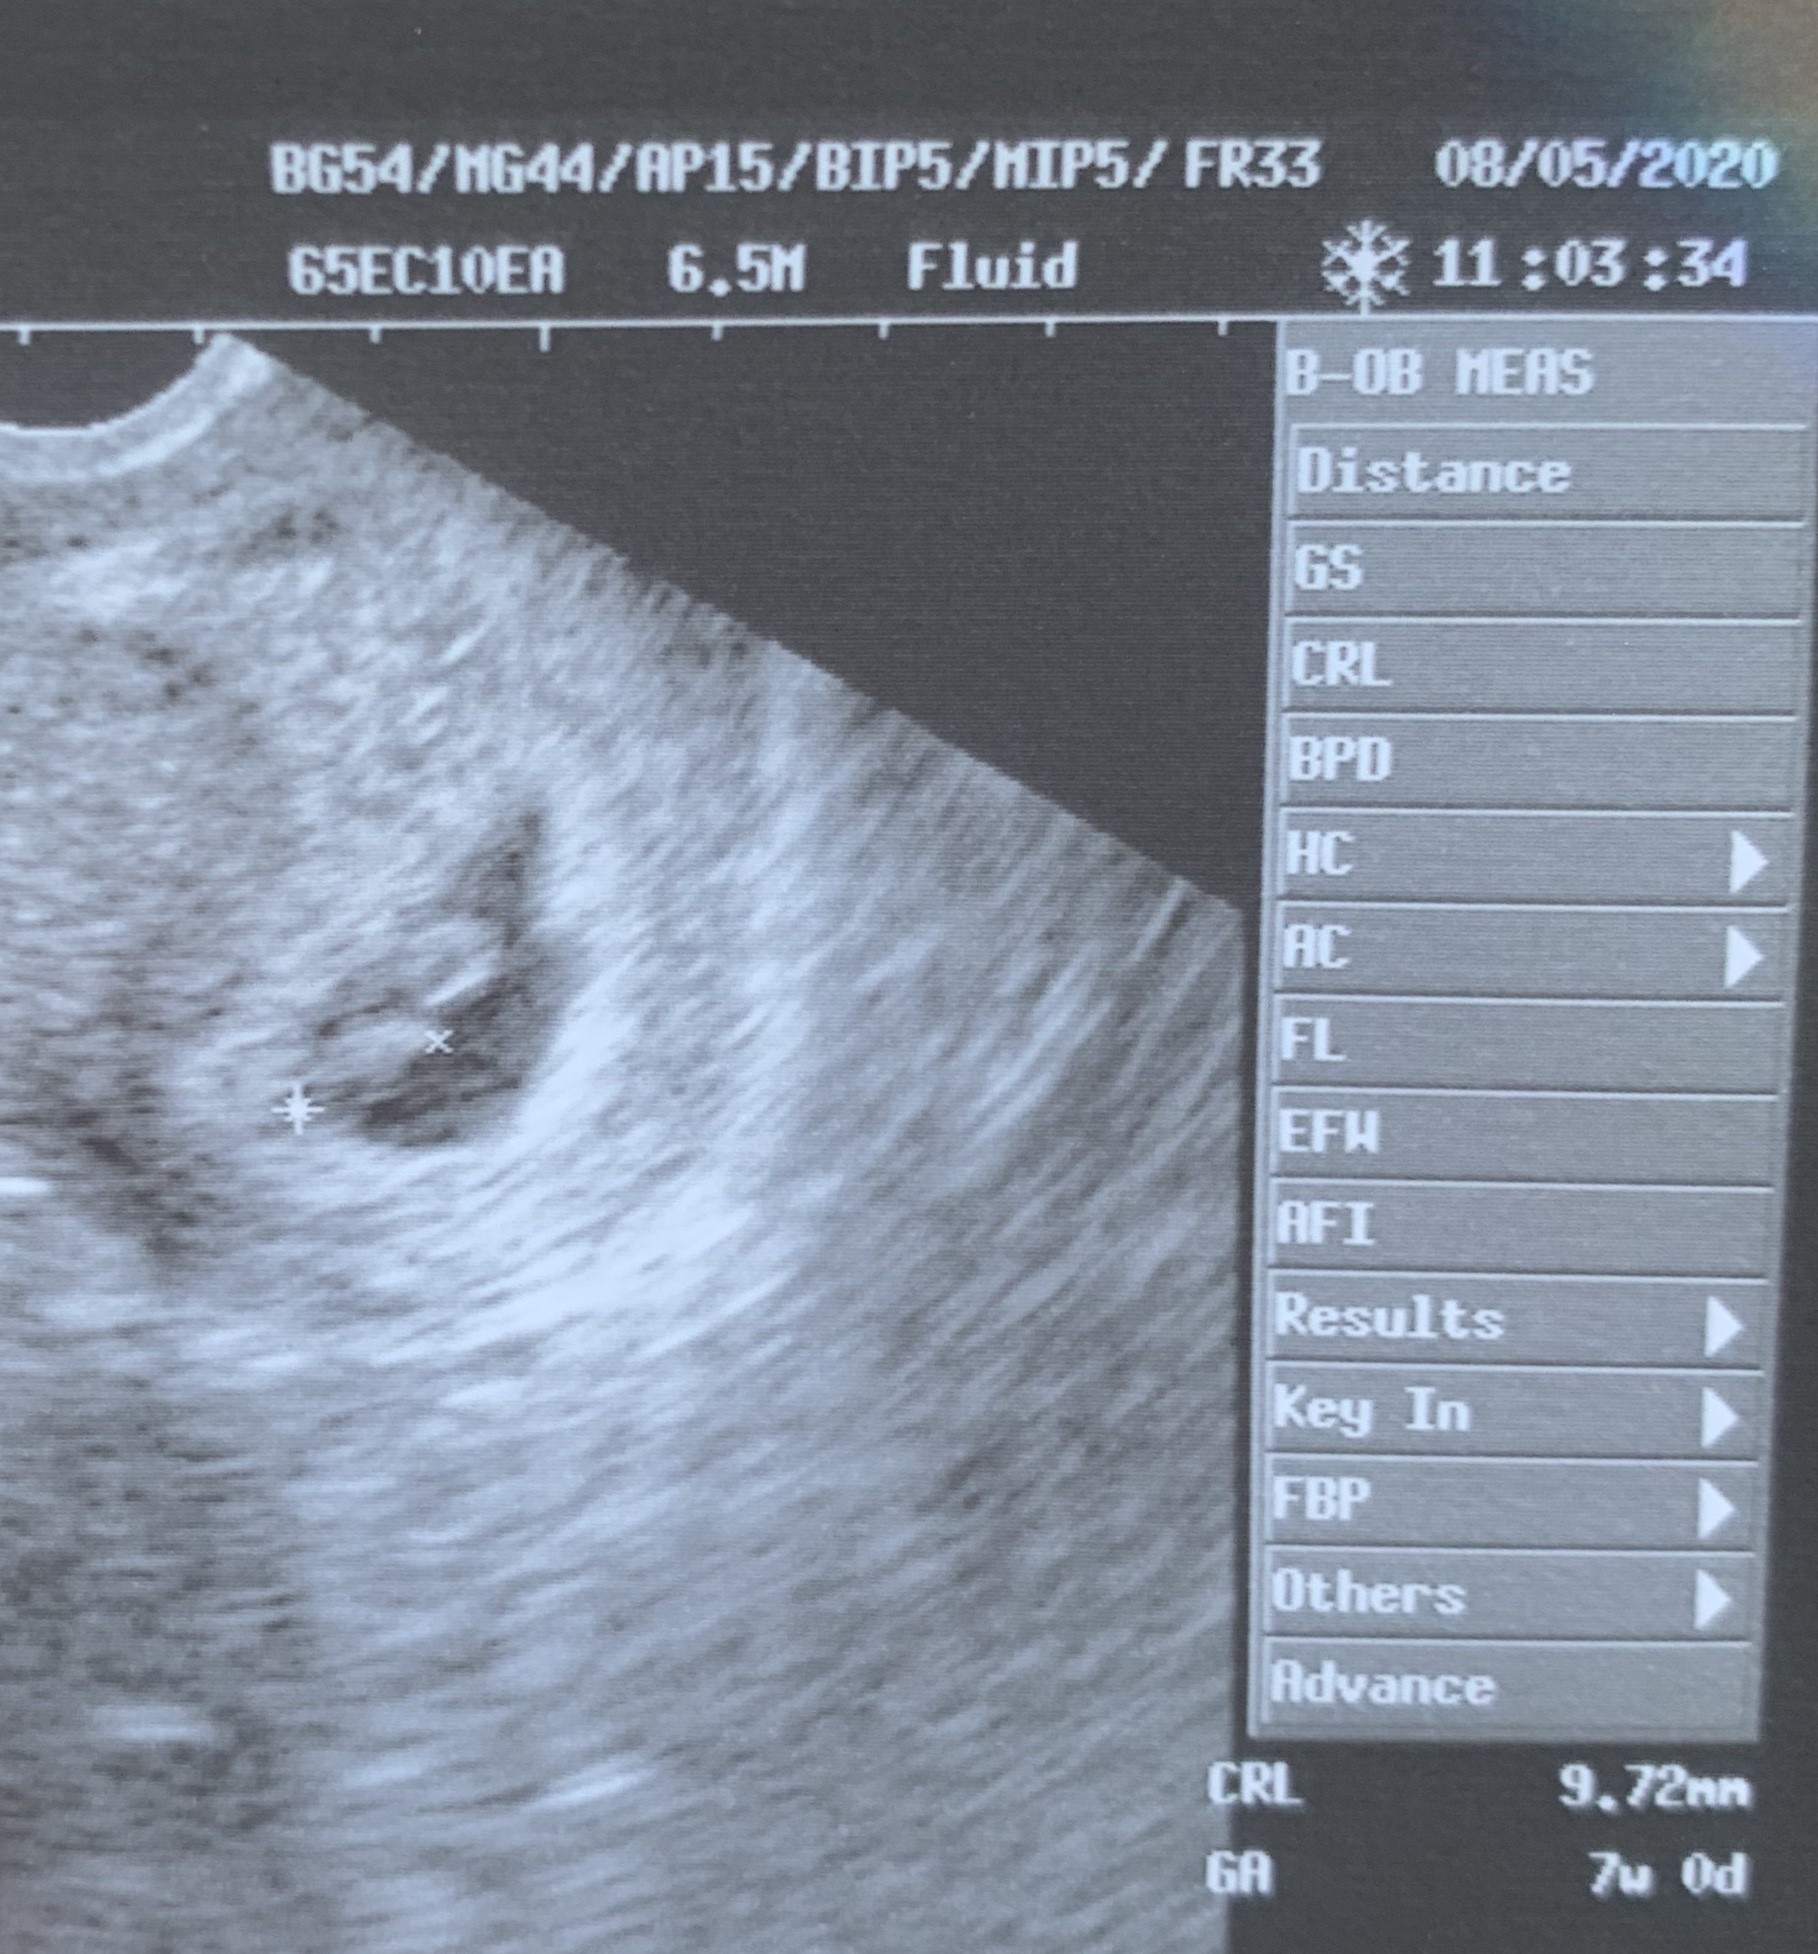

Mam do was pytanie. Byłam na usg, lekarz nie mógł mi powiedzieć czy to ciąża pojedyncza czy bliźniacza. Na usg widać zarodek z serduszkiem oraz drugą plamkę nie wiele mniejszą bez serduszka. Czy to może być pęcherzyk żółtkowy ? Ale według mnie jest trochę za duży jak na 7 tydzień ciąży. Lekarz powiedział ze na ta chwile nic niepokojącego nie widzi. Zobacz załącznik 1117098